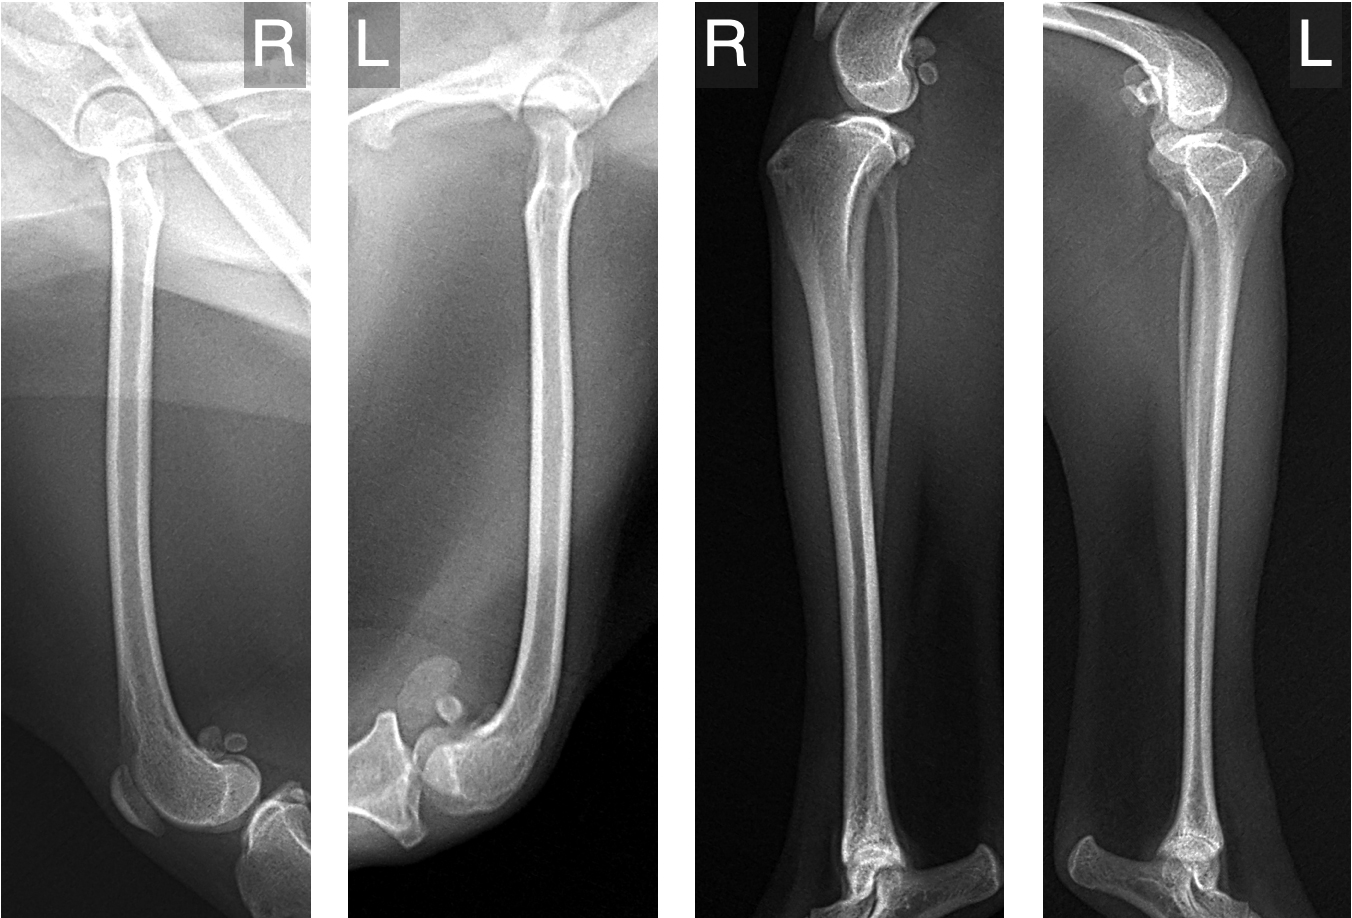

以下は、グレード4の膝蓋骨脱臼でよくみられる骨の変形の一例です。

ただし、骨の変形は症例ごとにその部位や程度が異なるため、CTによる三次元的な形態解析を行うことが、適切な手術計画を立てるうえで重要です。

レントゲン検査で骨の変形が疑われる場合には、より詳しい評価のためにCT検査をおすすめしています。

レントゲンでは全体像はつかめても、骨の捩れや傾きといった詳細な情報までは正確に把握できないことがあるからです。